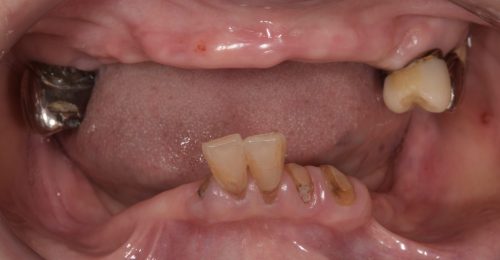

• オールオン4(上顎4本下顎4本)

術前

術後3年以上

年齢・性別 75歳・女性

治療期間 5ヶ月、通院回数18回

治療費用 5,492,080円(税込)

治療内容 1年前に作った入れ歯が痛くなり噛めない。バネも歯肉に刺さると来院。今回は入れ歯ではなくしっかり噛みたいということでオールオン4を希望。